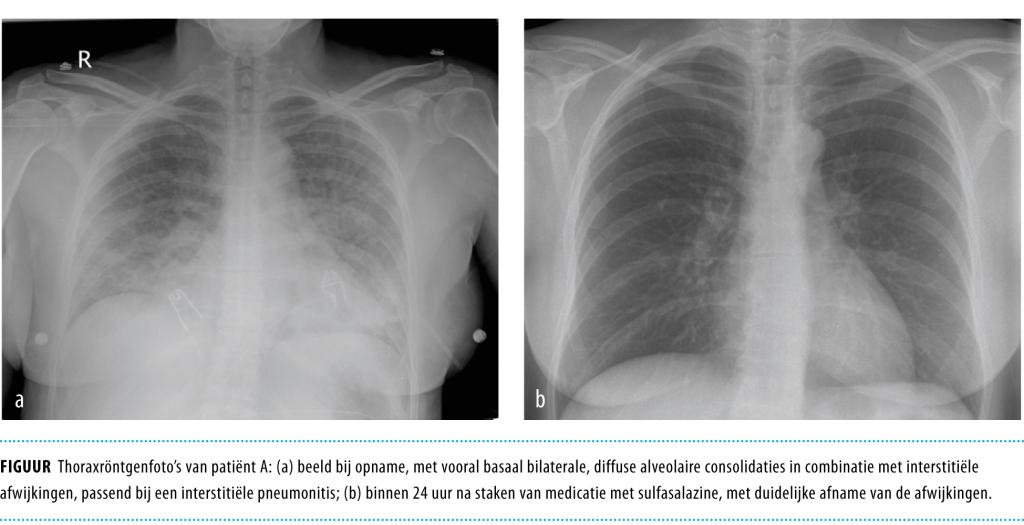

Patiënt A betreft een 43-jarige vrouw, bekend wegens de ziekte van Crohn, die op dat moment in remissie was. Zij gebruikte mesalazine als onderhoudsbehandeling. In verband met gewrichtsklachten was de mesalazine vervangen door sulfasalazine. 7 dagen na de medicatiewissel meldde patiënte zich op de Spoedeisende Hulp. Zij had sinds 5 dagen koorts tot 41°C, huiduitslag en een niet-productieve hoest. Bij lichamelijk onderzoek werd een zieke vrouw gezien met een lichaamstemperatuur van 39°C, tachycardie, tachypneu en met diffuus verspreide erythemateuze huiduitslag. Bij auscultatie waren grove ronchi beiderzijds basaal te horen. Laboratoriumonderzoek toonde een verhoogde CRP-concentratie (269 mg/l) en een ongestoord leukocytengetal van 7,5 x 109/l, zonder eosinofilie. De thoraxröntgenfoto liet bilaterale, diffuse alveolaire consolidaties zien in combinatie met interstitiële afwijkingen (figuur a). Op verdenking van een atypische pneumonie werd patiënte opgenomen en kreeg zij behandeling met ceftriaxon en gentamicine. De sulfasalazine werd gecontinueerd.

Figuur 1

De volgende dag werd patiënte vanwege respiratoire insufficiëntie overgeplaatst naar de Intensive Care voor intubatie en beademing. Vanwege aanhoudende koorts werden op de derde opnamedag de antibiotica omgezet naar amoxicilline-clavulaanzuur en ciprofloxacine, werd de sulfasalazine gestopt en werd prednisolon in hoge dosis gestart. De dag erop was patiënte koortsvrij, kon zij gedetubeerd worden en toonde de thoraxfoto sterke afname van de alveolaire consolidaties (zie figuur b). In de bloed- en sputumkweken groeiden geen micro-organismen. Serologisch onderzoek voor atypische verwekkers en respiratoire virussen had negatieve uitslagen.

Nadat patiënte verder herstelde, werd op opnamedag 10 de prednisolon gestaakt en de sulfasalazine herstart. De volgende dag was zij hypotensief en tachycard, had zij hoge koorts en reactiveerde de erythemateuze huiduitslag. Door deze onbedoelde re-expositie werd duidelijk dat er sprake was van een sulfasalazine-geïnduceerde interstitiële pneumonitis. Na het opnieuw staken van de sulfasalazine herstelde patiënte snel. Poliklinisch heeft zij nog enige tijd mesalazine gebruikt, zonder problemen.